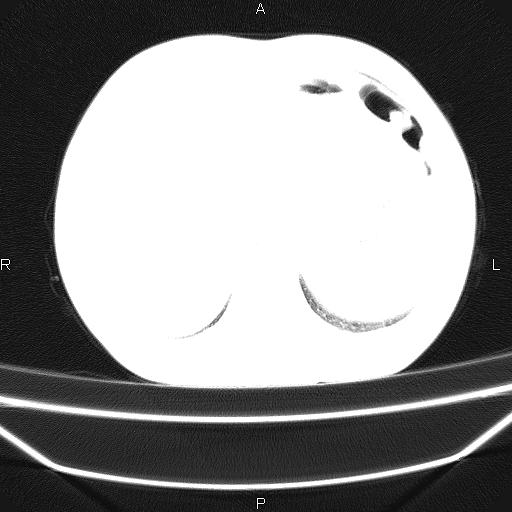

患者,男,40岁。间断发热,咳嗽二十余日。体温最高达38.9° 在当地诊所抗炎治疗三天后体温降至正常,患者自行停药。今又发热。胸片示,左下肺阴影。

左下肺片状高密度影,境界模糊,密度不均,考虑感染性病变可能性大,建议抗炎治疗后复查。左肺门增大,不除外占位性病变,必要时支气管镜检。

考虑感染性病变可能性大,抗炎后复查,占位不排除。

建议强化或纤支镜观察,考虑肿瘤性病变可能性大